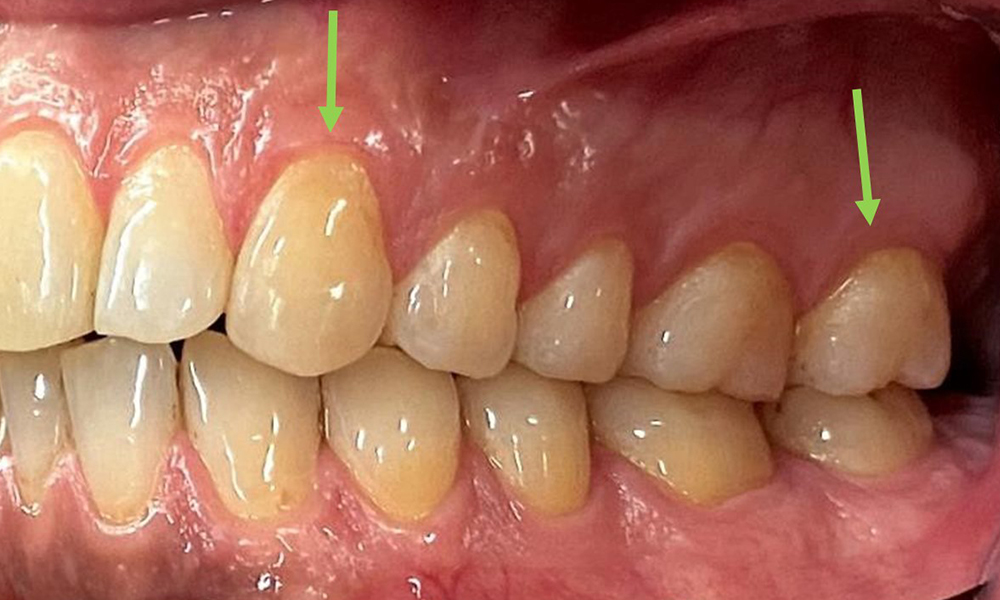

Dental zeigt sich ein vollbezahntes Gebiss mit 28 Zähnen. Auffällig sind Erosionen und Attritionen

(Abb. 4, Abb. 5). Der Patient trägt seit vielen Jahren nachts eine Schiene mit adjustiertem Aufbiss aufgrund Bruxismus. Die Erosionen sind auf den langjährigen Konsum isotonischer Getränke zurückzuführen. Parodontaler Knochenverlust und aktive kariöse Läsionen sind nicht vorhanden.

Nahaufnahme der Zähne

Abb. 5: Nahaufnahme der Zähne 45-47. Grüne Pfeile zeigen Attritionen und Erosionen im Bereich der bukkalen Höcker mit partiellem Schmelzverlust, © Dr. R. Krapf